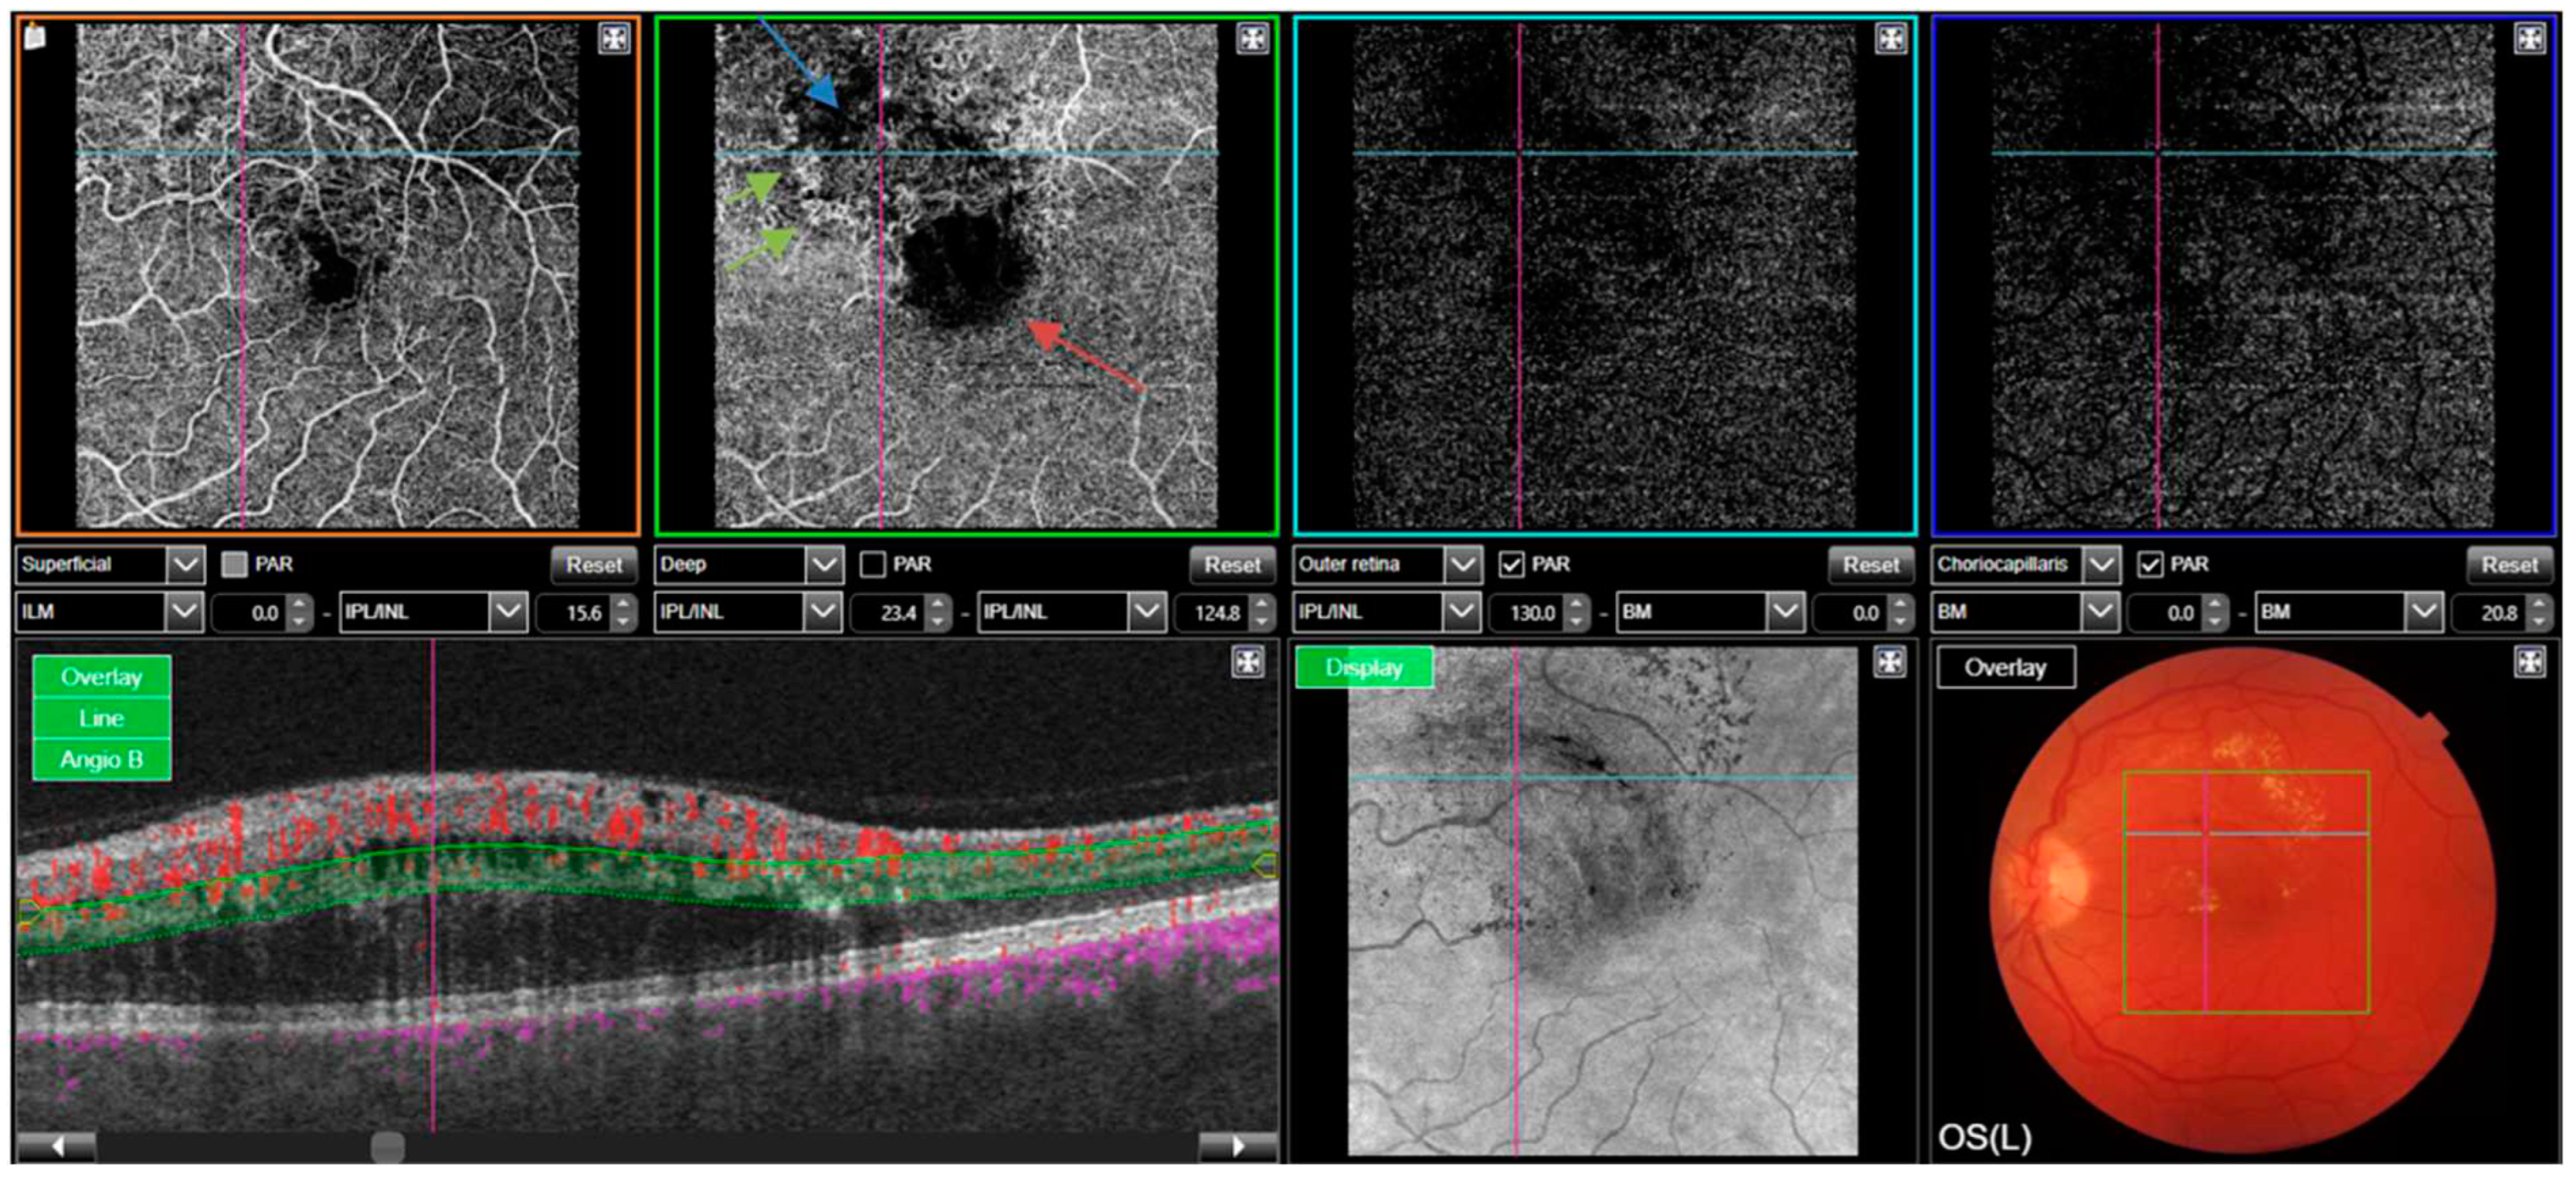

A representative case of OCT-A in RVO is depicted in Figure 3.

Figure 3. Left eye macular OCTA: A patient with superior macular branch retinal vein occlusion. The deep vascular plexus slab (green) shows widened, irregular foveal avascular zone (red arrow), capillary drop-out (blue arrow) and telangiectatic vessels at the borders (green arrow).